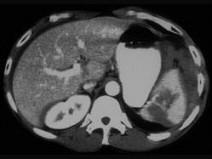

下列图像最佳诊断是 ( )A、脾破裂B、结肠破裂C、胰腺损伤D、小肠破裂E、肝破裂

问题 下列图像最佳诊断是 ( )

选项 A、脾破裂 B、结肠破裂 C、胰腺损伤 D、小肠破裂 E、肝破裂

答案 A